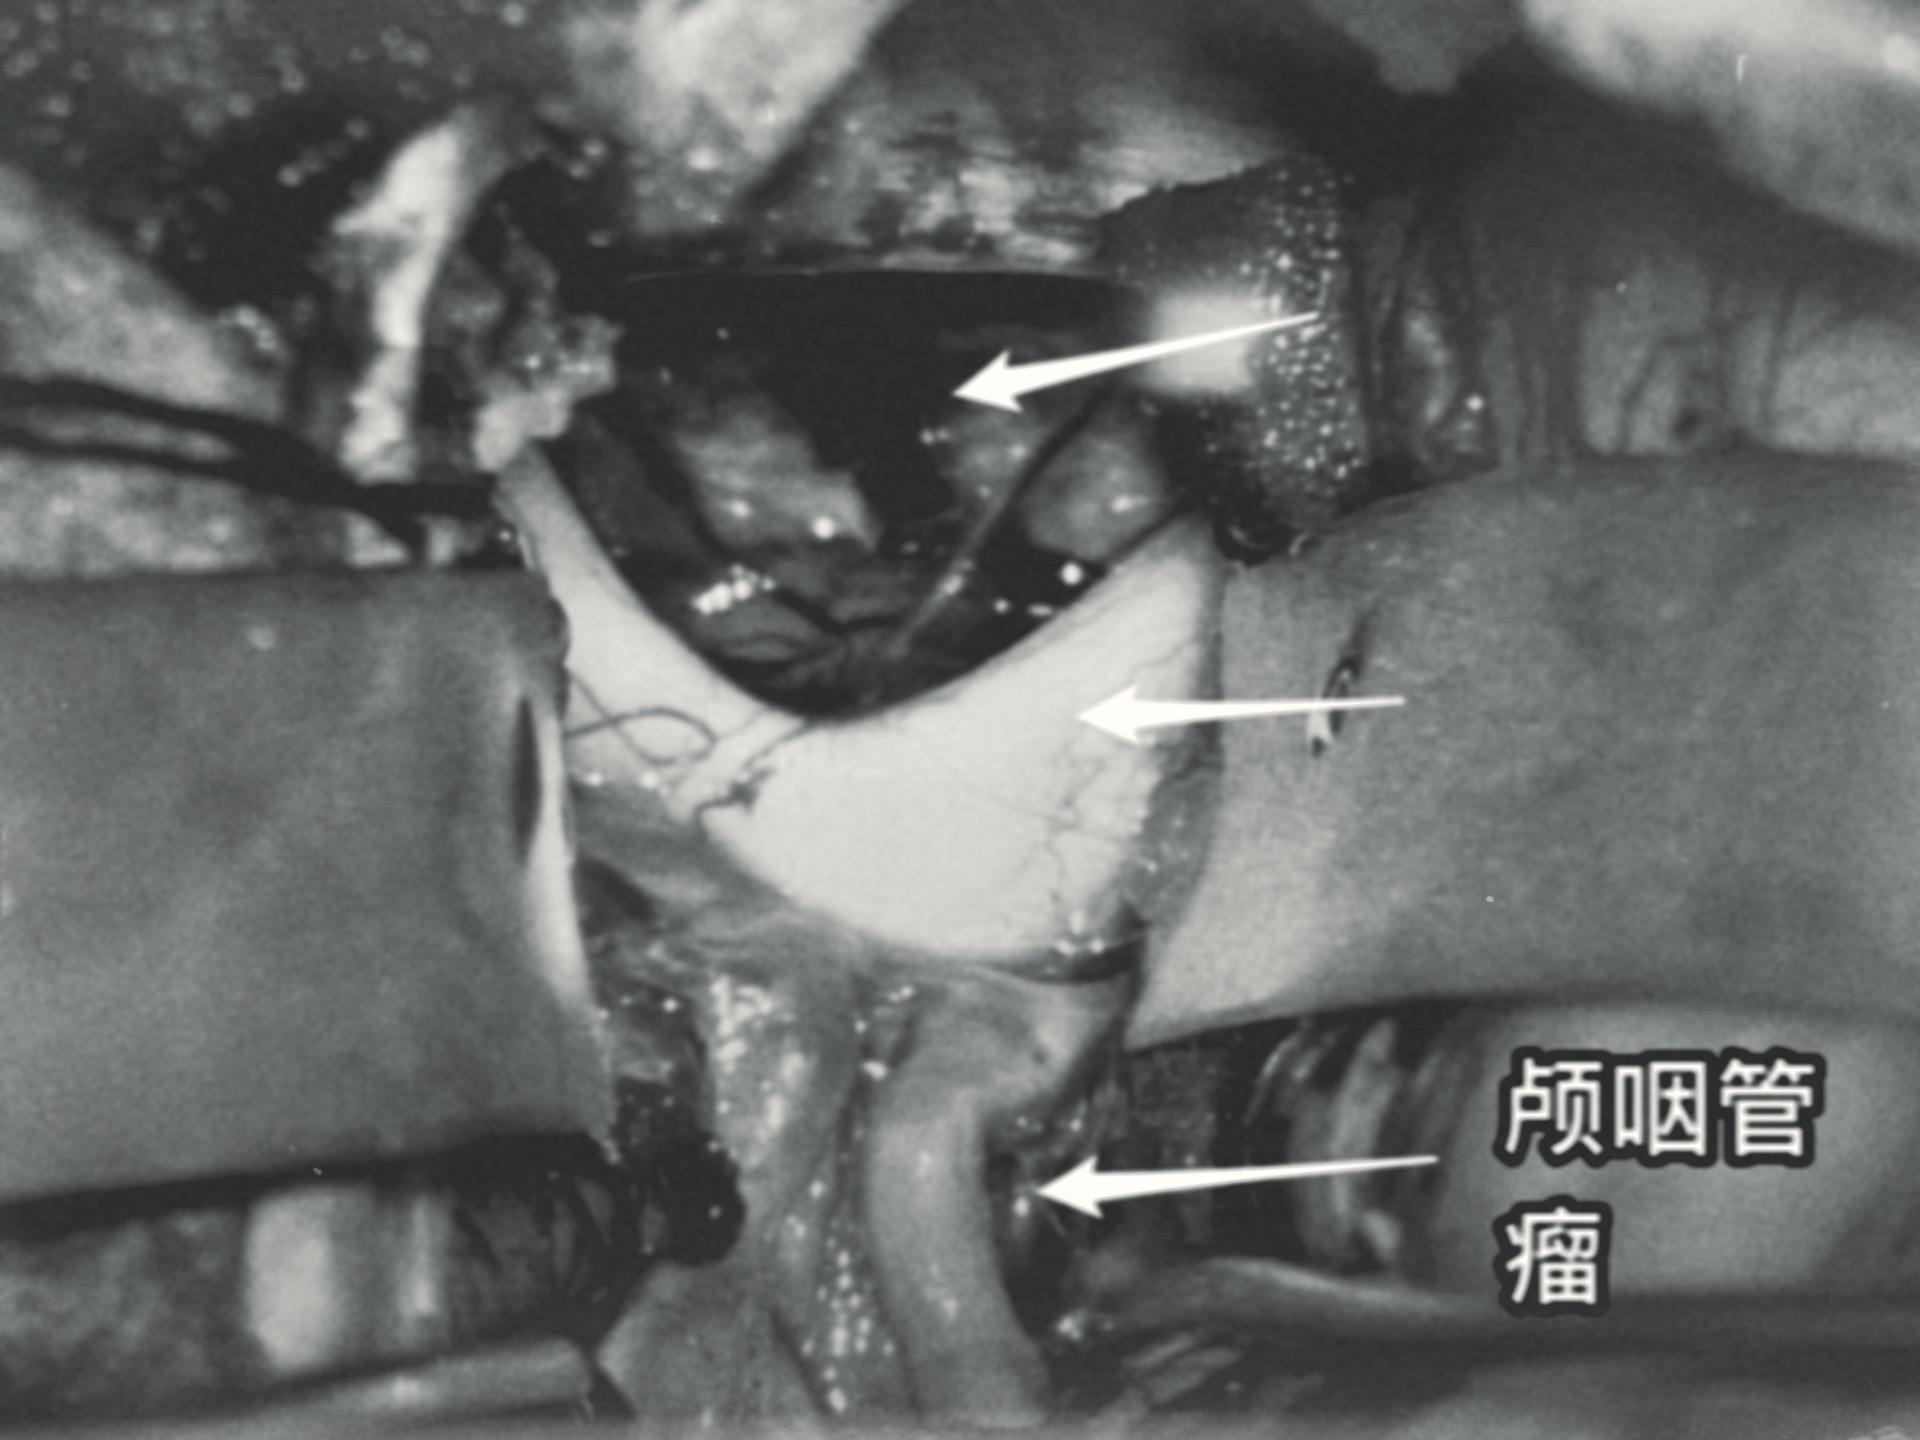

5月31日的颅咽管瘤手术。41岁山西男性,因思维糊涂、记忆力差发现鞍区肿瘤,为乳头型颅咽管瘤。 常规的经额底纵裂入路,将肿瘤完全切除。手术后病人的精神状态很好。 五月份的一共完成21台手术,其中20台为颅咽管瘤(今年一共80个颅咽管瘤手术),另一台为鞍区皮样囊肿! 在神经外科界,鞍区肿瘤的治疗是很有挑战性的![呲牙